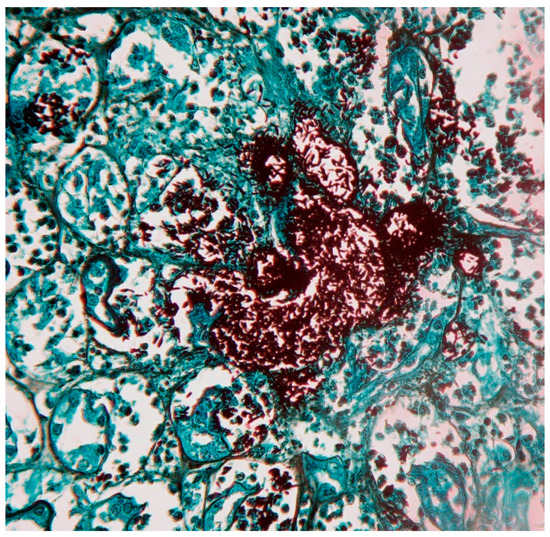

Cultures from exudative lesions, scale, tissue fragment, sputum and blood are the gold standard for diagnosis. Sabouraud dextrose agar with and without antibiotics, incubated at 28 °C is often useful; the colonies may develop between 5 and 8 days; because of its dimorphic feature, Sporothrix spp. can produce yeast colonies (blood agar, chocolate agar, BHI agar) in rich media, incubated at 37 °C; this must be distinguished from bacterial colonies. S. schenckii (sl), presents filamentous colonies with thin 1–3 micron septate, branched, hyaline hyphae, reproduce by ovoid, round and pyriform microconidia, derived from the denticle (sympudolic) form of conidiophores (10 to 30 μm in length) or directly from the hyphae; microscopically appear as “peach blossoms or daisies” (Figure 3) [3,4,11,24].

Figure 3.

Culture of Sporothrix schenckii (Sabouraud media, 28 °C) Filamentous state with thin hyphae and denticle microconidia like “daisy flowers” (Erythrosine, 40×).